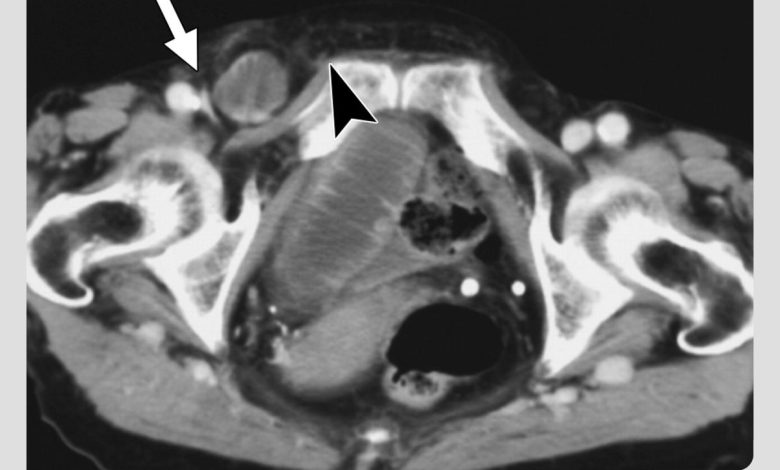

- MRI یا CT اسکن؛ در مواردی که معاینه و سونوگرافی کافی نباشد یا نیاز به برسی دقیقتر وجود داشته باشد.